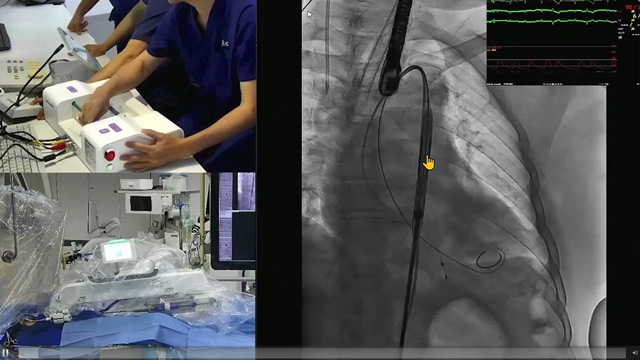

The use of adjunct devices in complex PCI

This session offers comprehensive education on the use of adjunct devices in complex PCI, focusing on different microcatheter designs and their optimal handling. It includes case-based illustrations demonstrating microcatheter applications, guidance on utilizing pre-shaped angled microcatheters in difficult anatomies, and the pivotal role of extension guide...